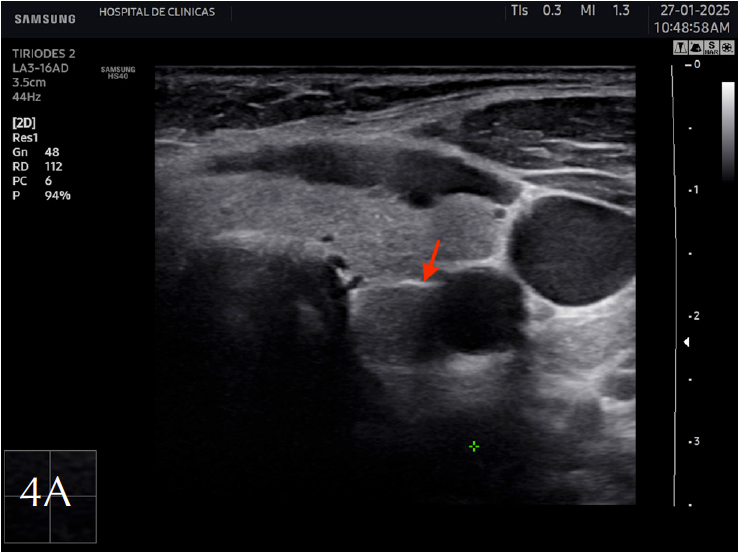

La eco estructura es homogénea, los márgenes son regulares y presenta una cápsula ecogénica, su vascularización es escasa. El rango de referencia para una tiroides normal es de entre cinco y diez vasos visibles dentro de la exploración de cada lóbulo valorado con Doppler color2. Se ha descripto que hasta un 50% de los individuos presentan lóbulo piramidal (Figura 3a y 3b). Este sector, en general, es similar en ecogenicidad, homogeneidad y vascularización al istmo y los lóbulos. En la superficie posterior de los lóbulos tiroideos, especialmente en el segmento inferior, puede visualizarse el tubérculo de Zuckerkandl, un ejemplo de este se puede observar en la figura 4a y 4b. Este es un tabique hiperecogénico fibroso que a menudo genera sombra posterior. Se forma por la extensión del tejido tiroideo de las áreas laterales de los lóbulos hacia el sector posterior, y a menudo exhibe una disminución de la ecogenicidad detrás del mismo. Este proceso puede imitar una lesión tiroidea o paratiroidea y causar dificultades en la interpretación2.